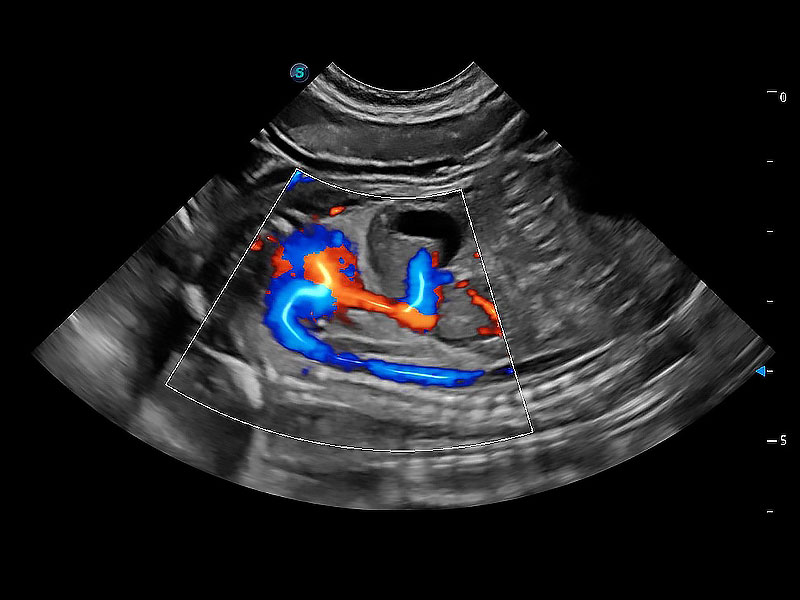

在傳統(tǒng)二維血流成像的基礎(chǔ)上,呈現(xiàn)血流的立體感,具有動感的生命力之美。即便是微小的血管也能輕松應(yīng)對,提高了血流的視覺敏感性。